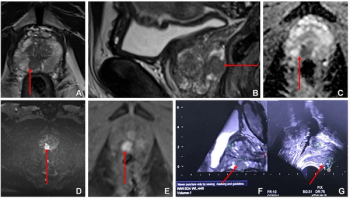

Combining multimodal imaging data and biopsy data, an artificial intelligence (AI) model provided enhanced sensitivity for defining prostate cancer tumor margins in comparison to conventional magnetic resonance imaging (MRI) assessments.